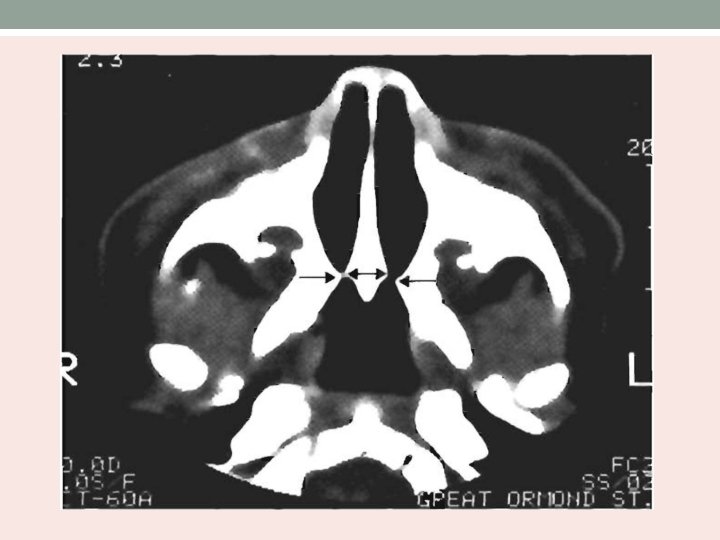

Investigations • Rhinography - administration of radiopaque dye into the nasal cavity. • CT scan -Confirm the diagnosis of choanal atresia (unilateral or bilateral). -Evaluate choanal atresia (vomer bone width). -Exclude other possible nasal sites of obstruction. -Determine the degree of bony, membranous, or mixed atresia. -Other abnormalities in the nasal cavity and nasopharynx.

Investigations • Axial view of CT scan nose/paranasal sinus showing bony choanal atresia • CT scan – thickness of atresia